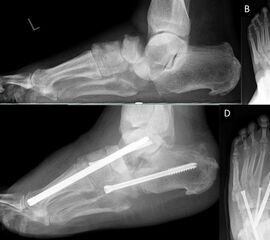

- Operative Behandlung von Druckstellen durch den Zusammenbruch des Fußlängsgewölbes

Als Folge der diabetesbedingten Neuropathie kann es zu dem sogenannten Charcotfuß kommen. Bei dieser Komplikation der Diabeteserkrankung kommt es häufig zu einer Zerstörung der Fußwurzelgelenke und -knochen. Dabei springen die Knochen aus den Gelenken (Luxation) und brechen (Fraktur). Der Fuß verliert an Halt und das Fußgewölbe kann zur Fußsohle durchbrechen (Plattfuß). Hierbei treten Druckstellen durch überstehende Knochenfragmente an der Fußsohle auf, die dann zu Hautschäden führen. Sollten hier konservative Therapiemaßnahmen (Polsterung/Schuhzurichtung) versagen, ist eine operative Korrektur angezeigt. Dabei werden die Knochen mittels Platten und langen Schrauben stabilisiert.

Zum Lesen der Bildbeschreibung und Vollansicht bitte Bild anklicken. Fotos: Alexander Mehlhorn